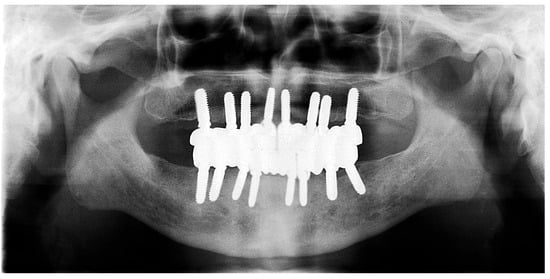

The restoration plan involved placing a bridge that connects the central incisors to the canines, along with an additional bridge spanning the first premolar to the first molar on each side of the maxillary arch. In the mandibular arch, the plan included three bridges: one connecting the lateral incisors bilaterally and another bridging the canines to the second premolars and first molars on each side (Figure 14 and Figure 15). Placing was confirmed using Panoramic radiographs obtained using the PantOs DG XP panoramic dental X-ray system (Fona S.r.l., Assago, Italy; CE 0051). The unit operates on a 230 V, 50/60 Hz input line with an 8 A fuse. Standard panoramic exposure parameters were applied (90 kVp, 10 mA, exposure time 14 s) following the manufacturer’s safety recommendations. A trained radiology technician performed all scans, and patient positioning was standardized using the built-in cephalostat support and light-beam alignment to ensure reproducibility of serial images.

Figure 13. Panoramic X-ray showing the inserted dental implants (taken 10 October 2022).

Figure 15. Panoramic X-ray showing the final prostheses (taken 21 November 2023).